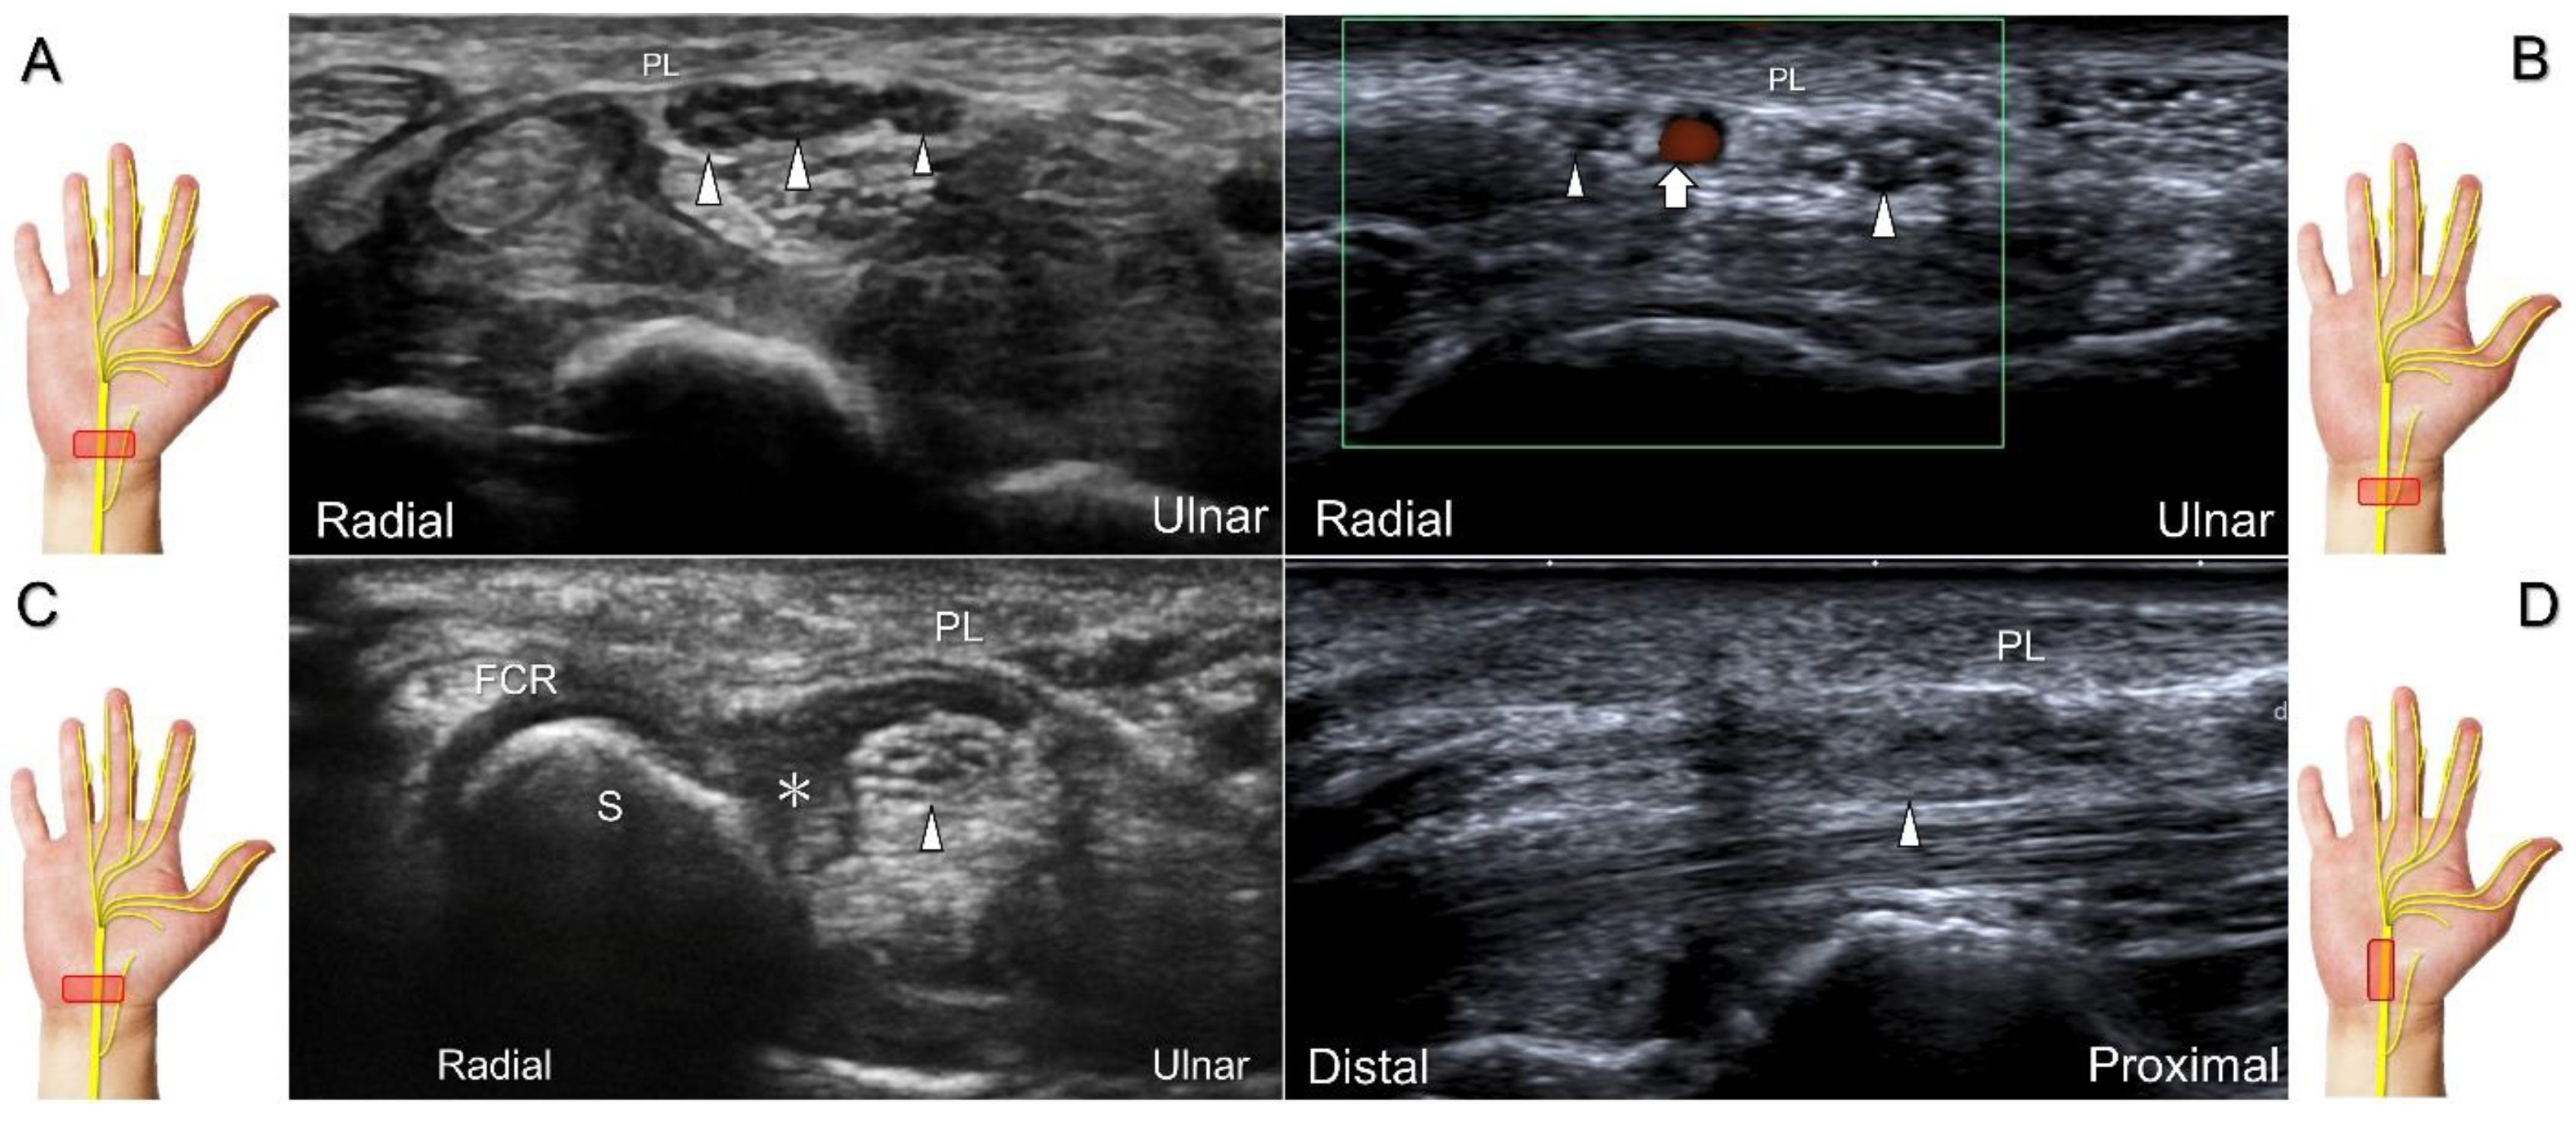

The nerve’s CSA (a cutoff value of 9–10.5 mm2) arises as the most useful parameter for the diagnosis [28], whereas its diameter, gliding resistance [29], stiffness (evaluated by sonoelastography), and intraneural vascularity (assessed by power Doppler imaging) may serve as adjuvant indicators. A bifid median nerve (Figure 4A), the presence of a persistent median artery (Figure 4B) with or without thrombosis, accessory flexor digitorum superficialis muscle (Figure 4C), laceration of the palmaris longus tendon (Figure 4D), and schwannoma (Figure 5) can be associated findings for carpal tunnel syndrome [9].

Figure 4. Sonographic images show a bifid median nerve (A), a persistent median artery with a bifid median nerve (B), accessory flexor digitorum superficialis muscle (C), and laceration of the palmaris longus (PL) tendon with the compression of the median nerve (D). White arrowheads: median nerve; white arrow: persistent median artery; asterisk: accessory flexor digitorum superficialis muscle. FCR: flexor carpi radialis tendon; S: scaphoid.